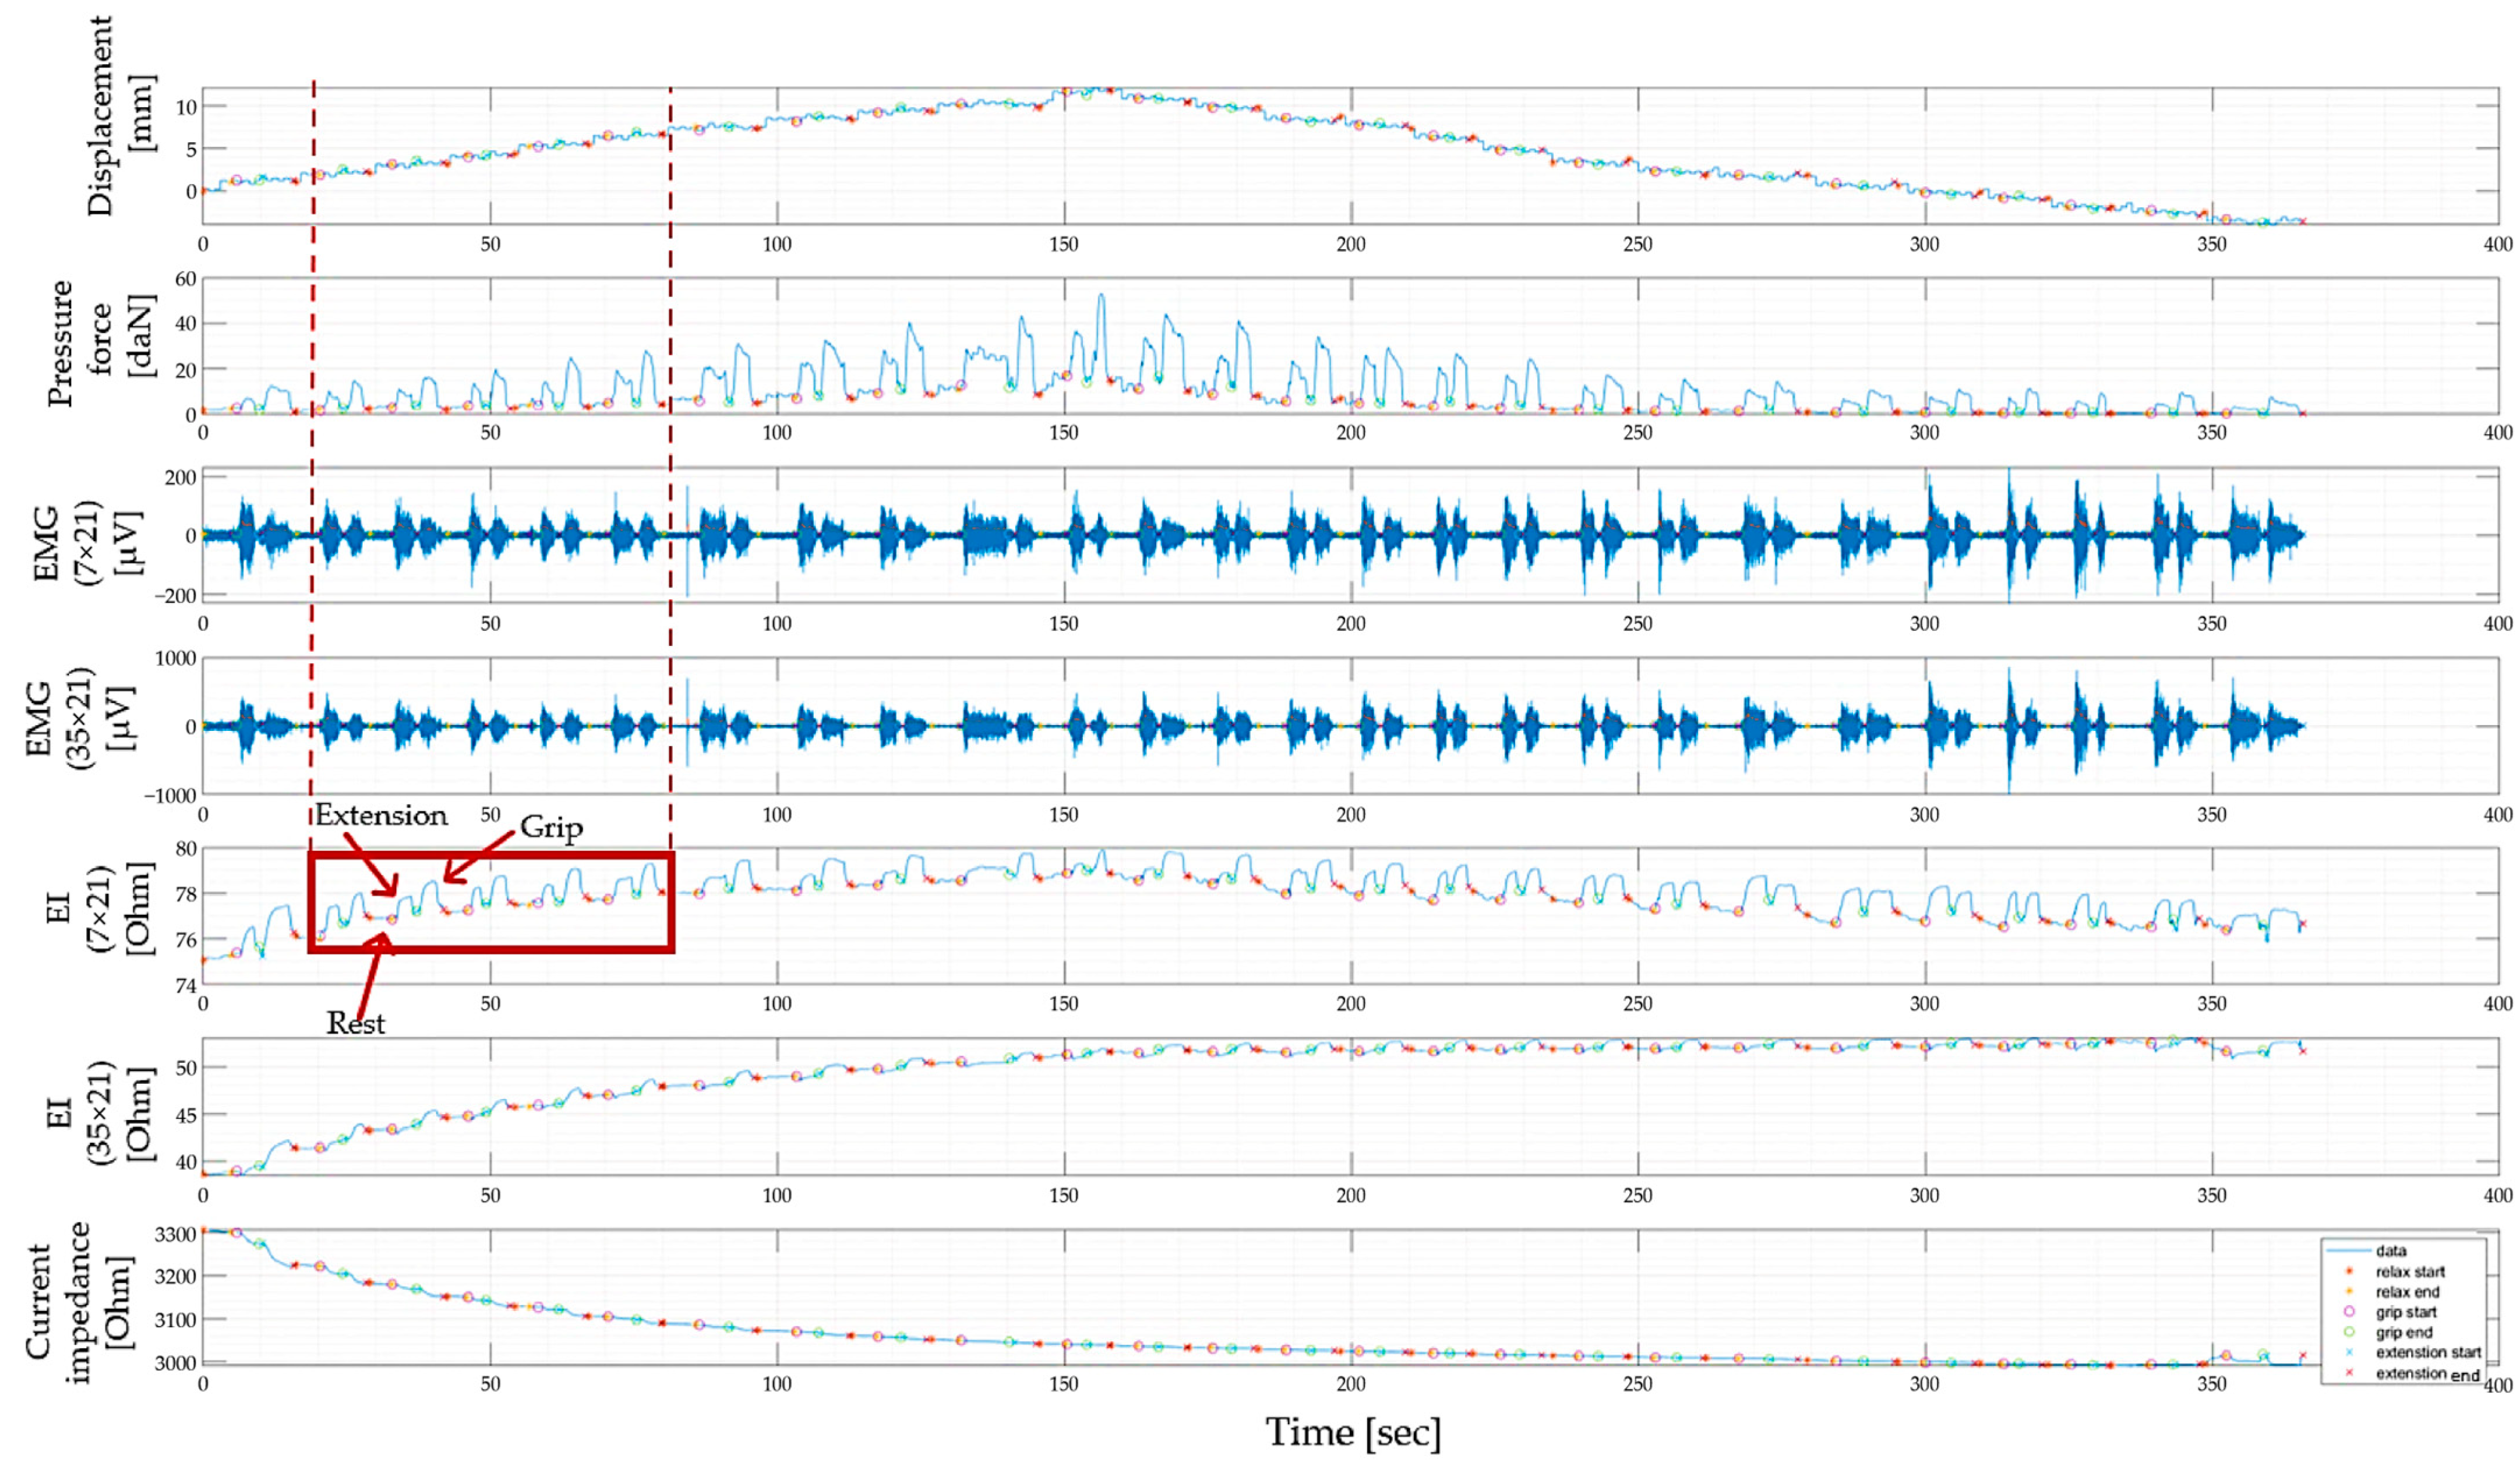

3.1. Study of Morphofunctional Activity of the Forearm Muscles When Performing Actions

3.2. Study of the Amplitude Parameters of the Electrical Impedance Myography Signal at Different Pressures of the Electrode System